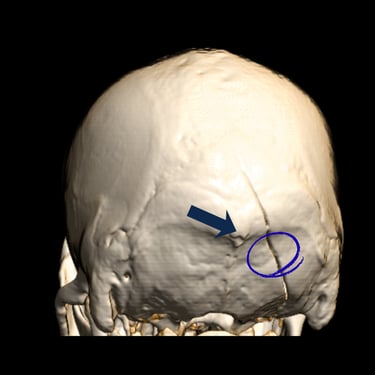

El trauma craneal severo es una de las principales emergencias neurológicas y puede poner en riesgo la vida del paciente. El diagnóstico por imágenes, a través de tomografía computarizada o resonancia magnética, es fundamental para identificar hemorragias, fracturas o lesiones cerebrales y definir el tratamiento adecuado. La evaluación temprana y la intervención oportuna por parte del neurocirujano permiten reducir complicaciones y mejorar el pronóstico neurológico. Una atención especializada y multidisciplinaria resulta esencial para garantizar la recuperación y preservar las funciones cerebrales.